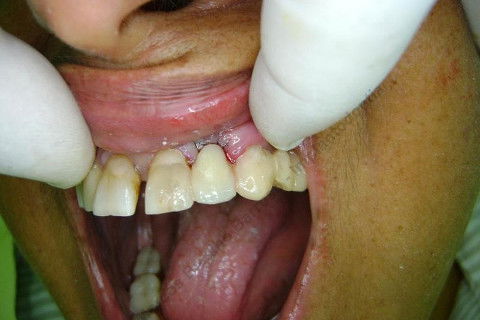

Paciente 66 anos, sexo feminino, procurou meus serviços para instalação de implante e coroa sobre implante na região do dente 22 com fratura radicular. Existem indicações para mais implantes mas a paciente está inrteressada no momento pela resolução deste caso.

Inicalmente estava planejado um implante cone morse 3.5 X 15,0 EX, mas resolvi experimentar um implante HI oferecido pelo vendedor da Bionnovation, como brinde (ele soube que estou preferindo o cone morse mas não trabalham com este sistema), e não consegui carga imediata neste implante. O travamento não foi satisfatório, ficou com um pouco mais de 20 N, menos de 25 N. Apesar desta ocorrência isto não significa que dará problema, apenas não fiz com carga imediata, aguardaremos 4 meses para a osseointegração.

Fotos do caso